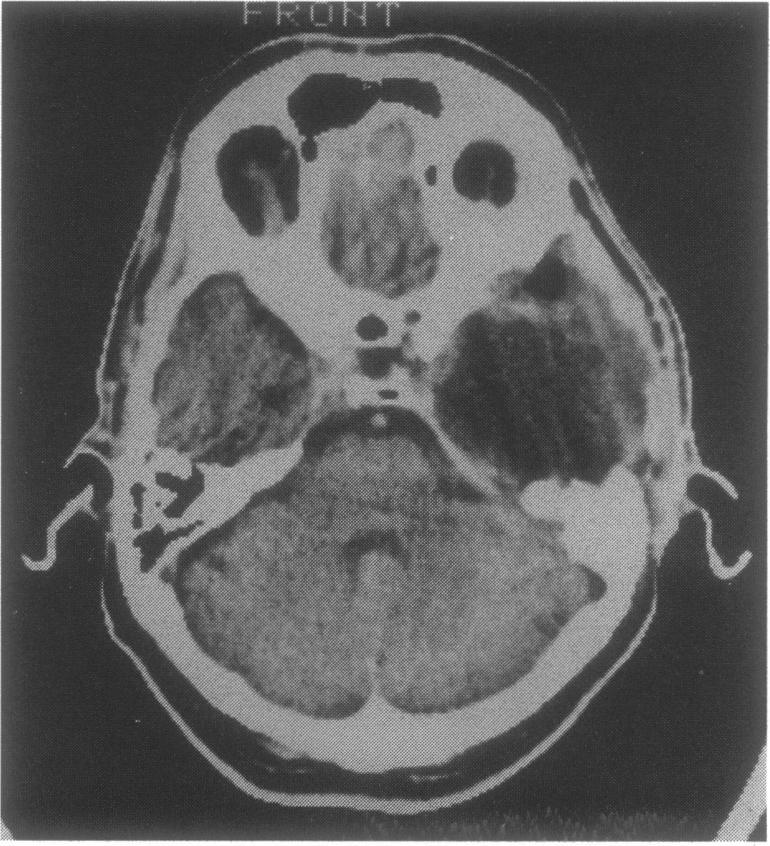

A case of a basal middle fossa giant cell tumor occurring in a 46-year-old man is described. The lesion appeared at the computed tomography (CT) scan examination as an hypodense mass with a peripheral "ring-like" enhancement, and no evident erosion of the skull base. The tumor, which infiltrated the basal temporal parenchyma, was removed via a temporal transzygomatic craniotomy, and extensive drilling of the petrous bone. Despite the occurrence, of significant postoperative complications, the patient ultimately showed a good clinical outcome, with no signs of recurrence at the 1-year follow-up CT scanning. The clinical and diageostic aspects and the management policy, of this rare lesion are discussed.

本文描述了一例发生在一名46岁男性的颅中窝底巨细胞瘤。在计算机断层扫描(CT)检查中,该病变表现为低密度肿块,周边有“环状”强化,且颅底无明显骨质侵蚀。肿瘤侵犯颞叶底部实质,通过颞部经颧弓开颅术及广泛磨除岩骨将其切除。尽管术后出现了严重并发症,但患者最终临床效果良好,术后1年的CT扫描未见复发迹象。本文还讨论了这种罕见病变的临床和诊断方面以及治疗策略。